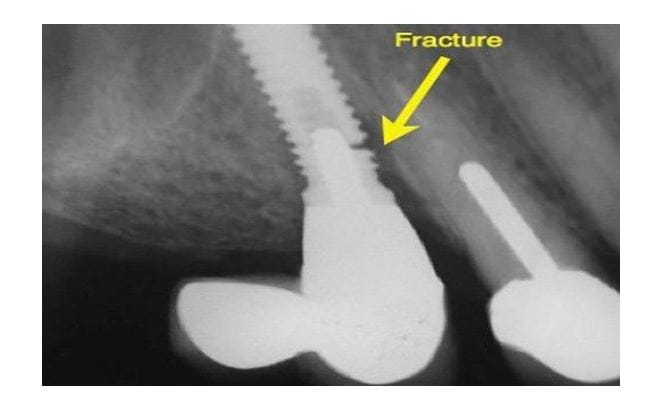

- Chipping or fracture of the crown

An implant system consists of 3 parts: the fixture (in bone) – the abutment – the crown. If any of these three components are not optimally designed from the beginning (especially occlusion and load direction), complications may arise after 2–5 years.